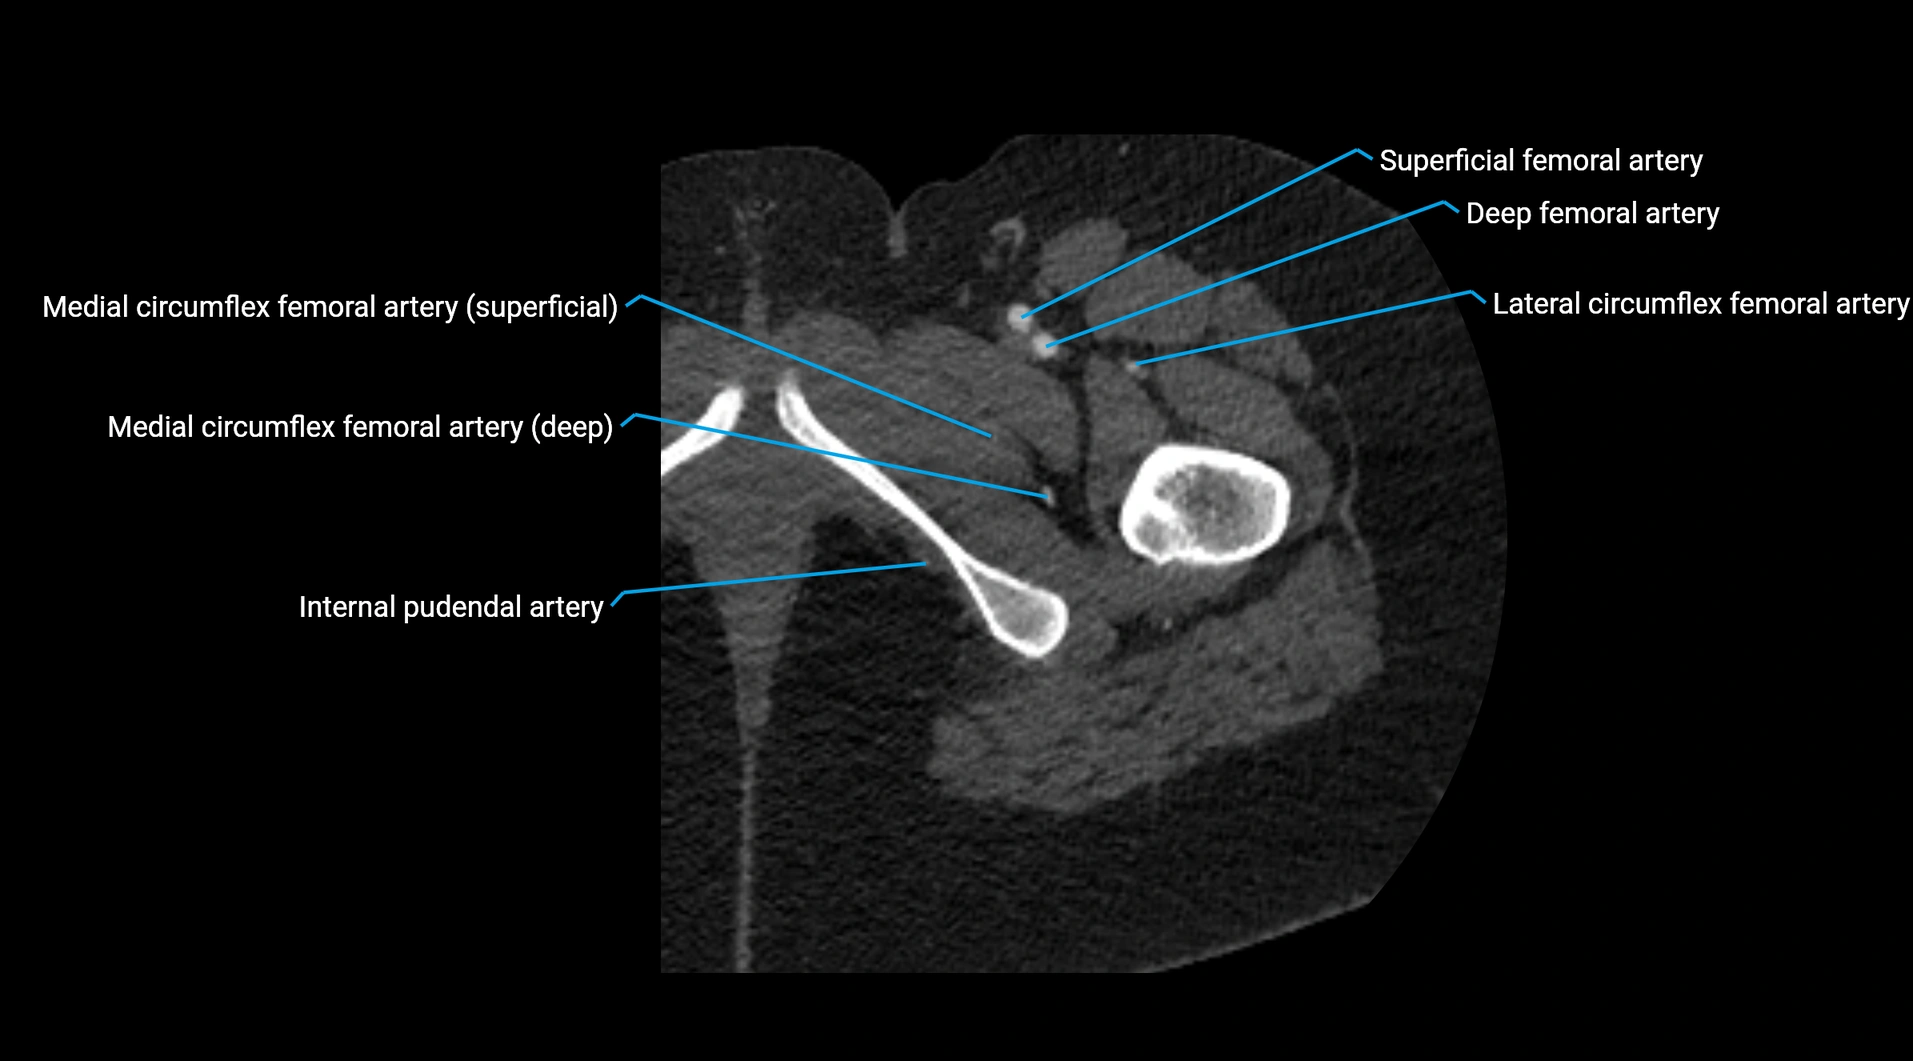

Contrast-enhanced CT (CTA):

• Gold standard for abdominal aortic imaging

• Provides excellent detail of lumen, wall, aneurysm, thrombus, and branch vessels

• Multiplanar and 3D reconstructions help in aneurysm measurement, stent graft planning, and dissection evaluation

• Detects acute rupture, traumatic injury, or occlusion with high sensitivity